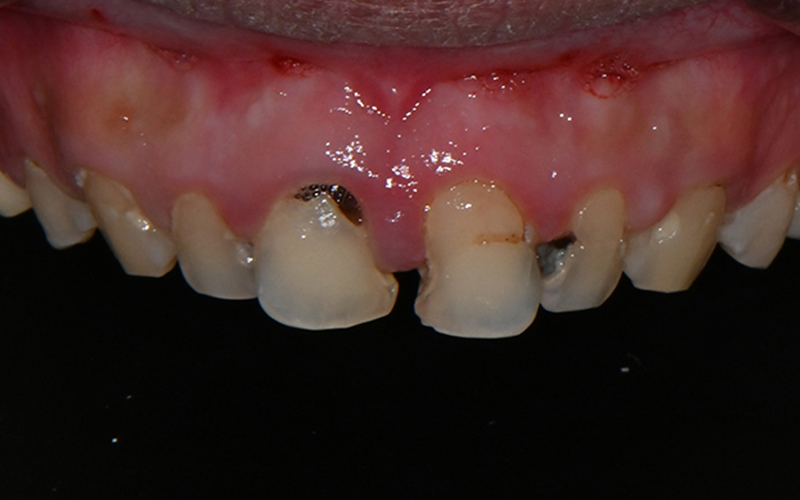

💛 초진 💛

소개해드릴 환자분은

충치가 여러 개 진행된 상태였고,

통증이 있다가 말다가 반복되어

더욱 치료 타이밍을 놓치기 쉬운 상황이었습니다.

실제로 진료기록에서도 확인되듯이

10개가 넘는 치아에 대해

신경치료(근관치료)를 받으셨고,

대부분 복잡한 염증과 신경 감염이

동반되어 있었습니다.

특히 윗니 앞니와 어금니까지

넓은 범위에 걸쳐

치료가 진행되었습니다.

파노라마 사진을 촬영해

정밀 체크를 진행하였고,

전체적인 치료를 계획하였습니다.

특히 앞니는 심미적으로도

눈에 띄는 부위이기에

섬세하게 고려하여 계획하였습니다.

치료전 쉐이드 가이드를 통하여

치아 색상 체크도 진행해주었답니다.

치료 전 사진을 보면 웃음을 짓기 어려울 정도로

앞니에 큰 충치와 손상이 있었고,

중간중간 레진으로 채워진 부분이

심미적으로도 큰 스트레스였다고 하셨습니다.